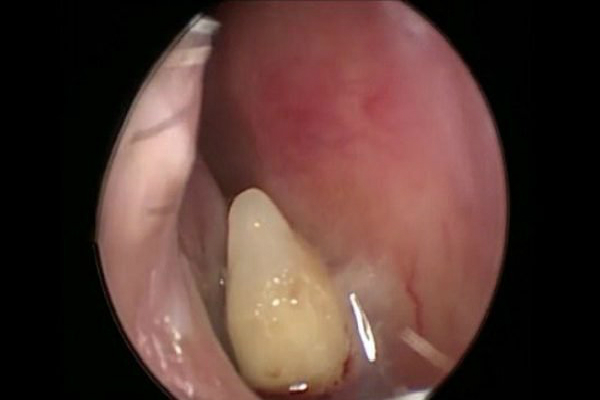

Nesse texto, os médicos contam que o paciente apresentava os seguintes sintomas: narina que parecia bloqueada por algo, coriza e olfato reduzido. Ao fazerem a análise do interior do nariz, eles perceberam que ele estava com a cartilagem do meio do nariz, o famoso septo, um pouco torta. Nessa hora, eles sentiram que havia algo preso na cavidade nasal. Então foi a hora de fazer uma tomografia. Foi quando descobriram que havia um dente nascendo no septo do paciente.

Para retirar aquele dente intruso de lá, foi necessário uma cirurgia endoscópica. Após a retirada do corpo estranho, a recuperação do senhor foi muito boa. Apesar disso, os médicos não conseguiram encontrar o porquê disso ter acometido o paciente. Ou seja, o motivo daquele dente ter nascido ali não foi encontrado.